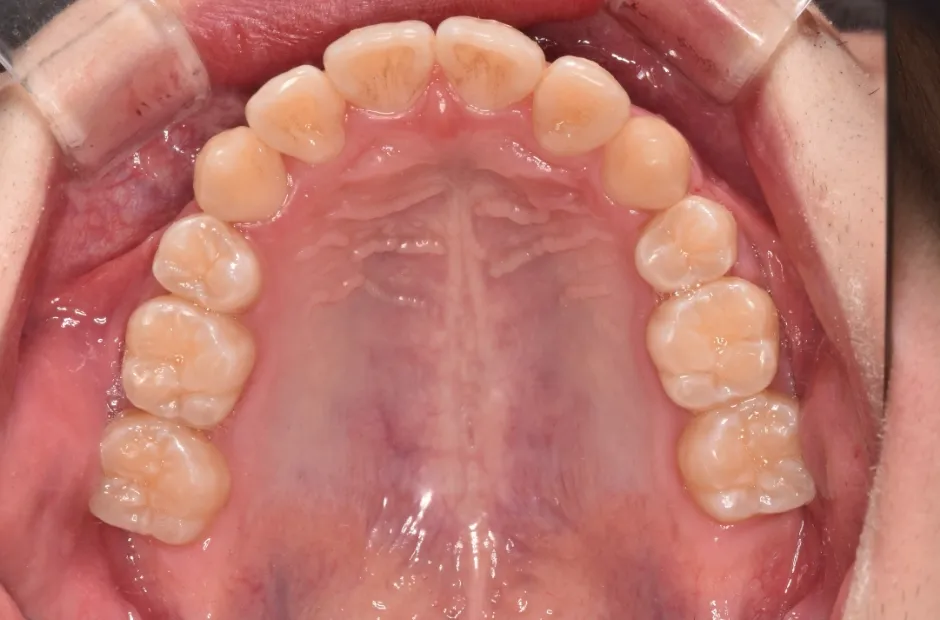

治療症例

ブラケット矯正

前歯部反対咬合

| 診断名・主訴 | 前歯部反対咬合 |

|---|---|

| 年齢・性別 | 14歳・男性 |

| 治療期間・回数 | 1年2か月 |

| 治療に用いた主な装置 | ブラケット矯正 |

| 抜歯部位 | なし |

| 治療費 | 60万円(税抜) |

| リスク・副作用 | 装置による違和感・疼痛・歯肉退縮・歯根吸収・虫歯のリスクなど |

治療前

治療後